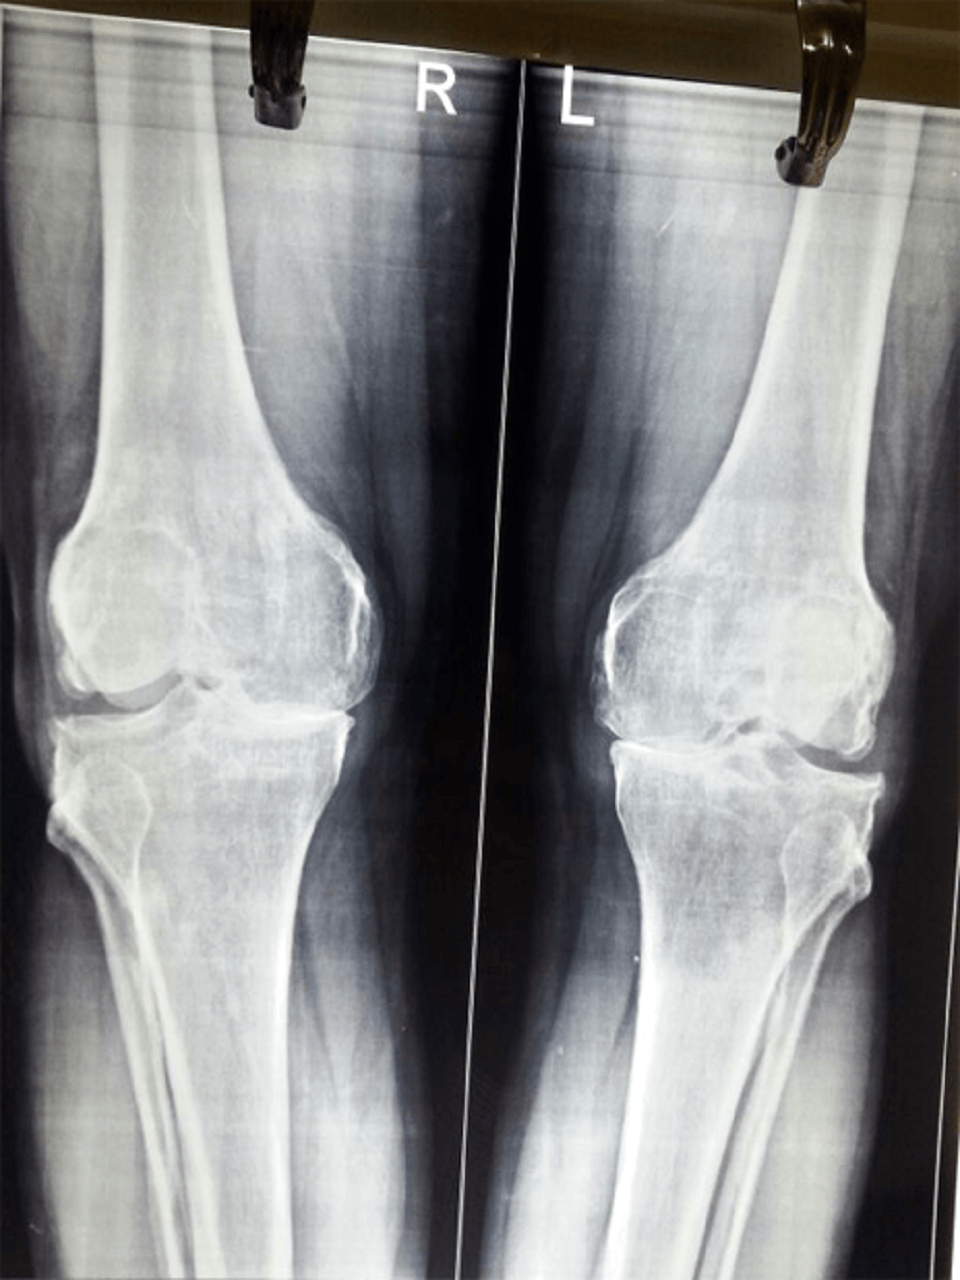

Bhanuben [ Total Knee Replacement ]